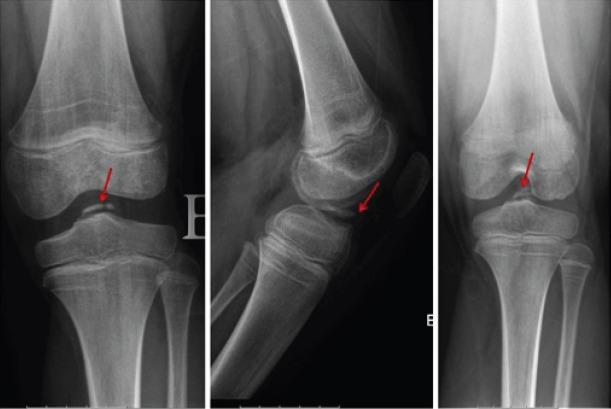

A 6-year-old boy with went to the emergency department after suffering trauma in his left knee. In the performed X-ray, no osteoarticular injury was identified. Conservative treatment with immobilization with cast was performed. After removing the immobilization, the initial evolution was positive with no pain on mobilization. A few months later, he went again to the emergency department due to new left knee trauma. On examination, he had pain in the mobilization of the left knee, especially in knee extension which was not entire. Image study led to the diagnostic of avulsion fracture of the anterior tibial spines. The fracture was classified as modified Meyers and Mckeever Type II and conservative treatment with cast immobilization was performed. In the clinical and imaging revaluation done 4 weeks later, an evolution to non-union of the anterior tibial spine was noticed. At arthroscopy, non-union of tibial spines was confirmed, with elephant paw bone fragment with loss of its right to domicile. Open surgery was performed with debridement, cruentation, and fixation of the bone fragment to the tibia with a screw. The patient had favorable post-operative evolution with fracture consolidation, preserved mobility, no instability of the joint, and no limitation in daily and school activities. Four years after the initial surgery, a second procedure was performed for the removal of the screw. During 7 years of follow-up, no limitations or sequels were found.

一名6岁男孩左膝受伤后前往急诊科。在进行的X线检查中,未发现骨关节损伤。采用石膏固定进行保守治疗。去除固定后,最初的恢复情况良好,活动时无疼痛。几个月后,他因左膝再次受伤再次前往急诊科。检查时,他左膝活动时疼痛,尤其是在不完全伸直时。影像学检查诊断为胫骨前棘撕脱骨折。该骨折被分类为改良迈尔斯和麦基弗II型,并再次采用石膏固定进行保守治疗。在4周后进行的临床和影像学复查中,发现胫骨前棘出现骨不连。关节镜检查证实胫骨棘骨不连,有象爪状骨块且失去原位。进行了开放手术,包括清创、植骨,并使用螺钉将骨块固定于胫骨。患者术后恢复良好,骨折愈合,活动度保留,关节无不稳定,日常和学校活动无受限。初次手术后四年,进行了第二次手术取出螺钉。在7年的随访中,未发现任何限制或后遗症。